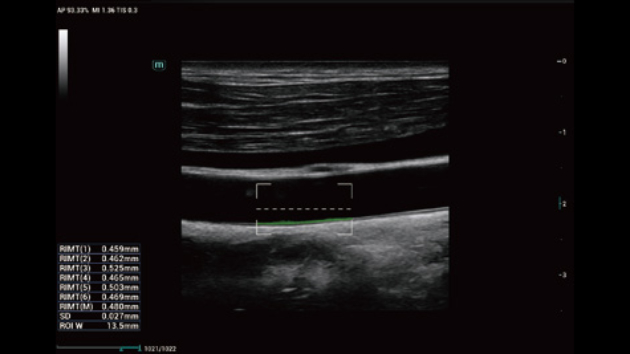

No matter your routine is in hospitals, clinics, or you are honing skills in General Imaging applications, women's health care or cardiovascular specialties, you will find highly powerful tools available on this series to keep you stay ahead.

Comprehensive Imaging Solutions Powered by ZST+

The ZST+ platform is an extraordinary innovation, representing an ultrasound evolution. Transforming ultrasound metrics from conventional beam-forming to channel data based processing. It overcomes the traditional trade-off limitation among spatial resolution, temporal resolution and tissue uniformity, delivering exceptional image quality for infinite imaging solutions with non-stop improvements.